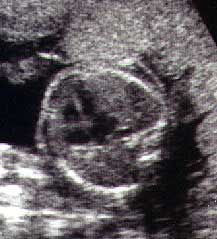

30 Неделя Беременности Развитие Плода Фото